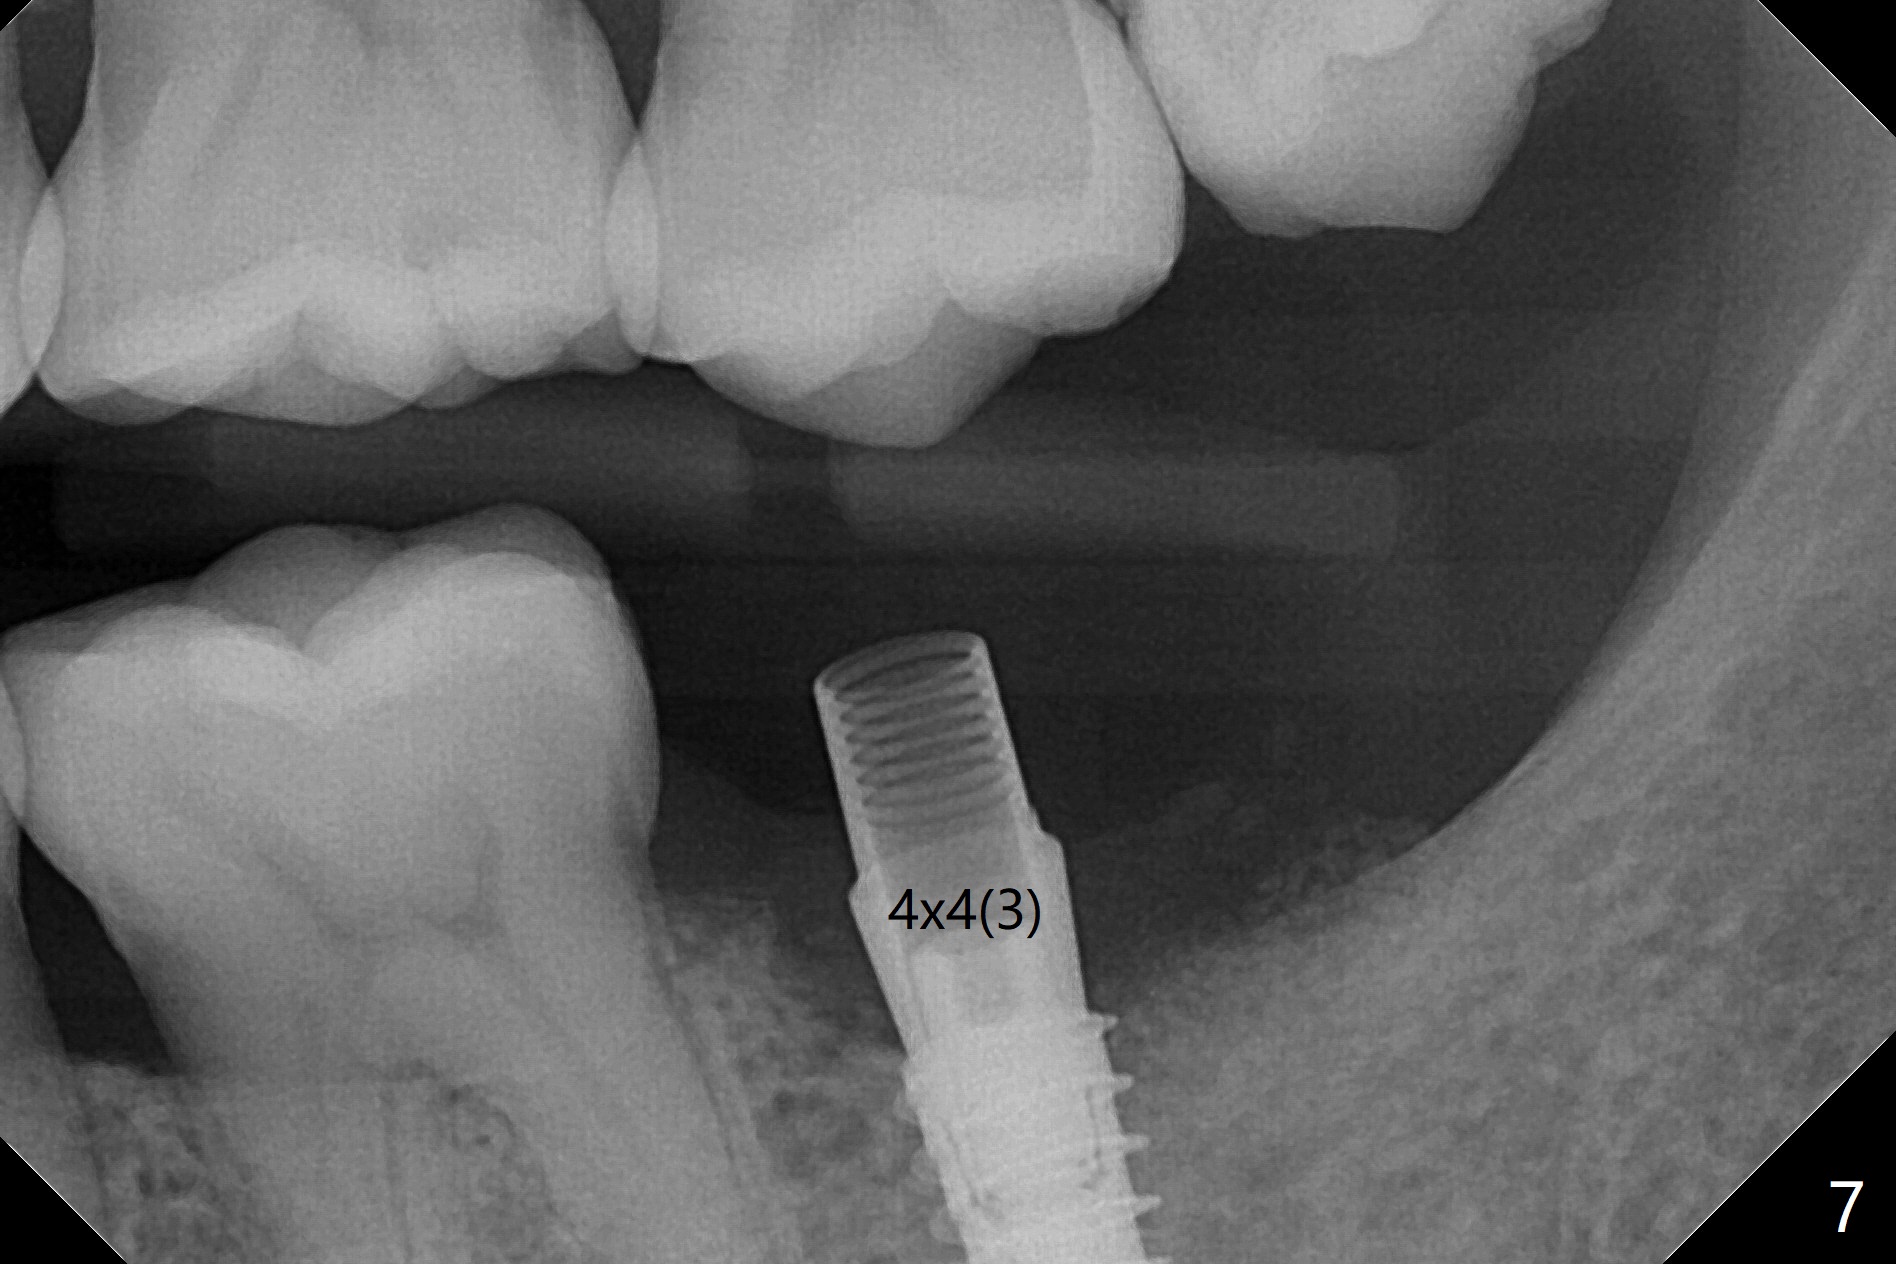

左下7钻洞中出现三种情况:容易出血(血小板减低(9万)),疼痛(根尖肉芽肿)和骨质疏松,钻洞深度还没达到,使用短小报废植体拍摄根尖片(图一),之后下颌牙槽神经阻断,钻洞没有疼痛,但是未注意骨质疏松问题,按照正常钻洞顺序,所以正式植体扭力低,10 Ncm(图二),放置骨粉和不可吸收膜,PTFE缝合(图三)。术后一周膜舌侧稍微外翻(剪太小些,图四)。病人将术后五周回来去除膜,之后拍摄咬翼片证实骨粉丧失与否。其实病人提前回来,抱怨缝线不适,膜不翼而飞(图五,折线后),患侧咀嚼,因为对侧下颌第二磨牙疼痛又不肯拔除。The bone graft placed at the time of immediate implant (Fig.3 *) is apparently changing into the normal bone 4 months postop before uncover (Fig.6). After removal of the bone coronal to the implant with a curette, a 4x4(3) mm pair abutment is placed (Fig.7). Two weeks later the abutment screw is torqued at 20 Ncm.